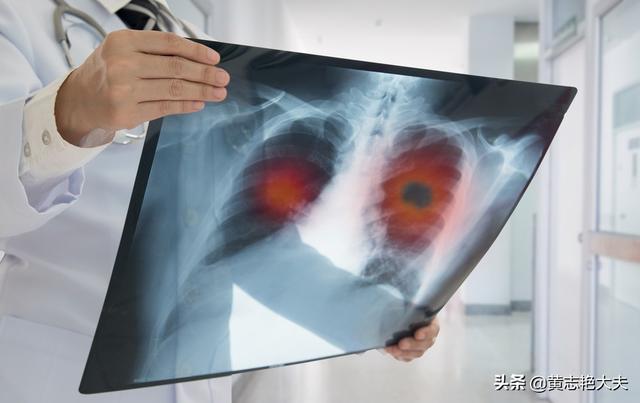

がん細胞は恐ろしいもので、脳転移や肝転移など、血管やリンパのあるところならどこにでも転移する。

このような巨大な肝転移が多発した場合、コントロールできなかったり、治療に反応しなかったりすると、短期間で進行する可能性がある。

進行した肺がんの多くは、肝臓、脳、骨に転移し、臓器不全に至ることがある。

(3) 腫瘍転移

進行した肺がんは、体内のさまざまな臓器に多発転移を起こすことがある。 肺がんは脳、肝臓、骨格椎体系に転移することが多く、脳転移は頭蓋内圧亢進症を引き起こすことがある。 脳のスペースが限られているため、がん細胞が増殖すると脳ヘルニアや頭蓋内圧亢進症を引き起こし、生命を脅かすことになる。椎体転移は、病的骨折や神経の圧迫を引き起こし、麻痺や死に至ることもある。多発性肝転移は、肝機能障害や肝不全を引き起こす可能性があります。

4.腫瘍転移、多臓器不全:肺癌の末期には様々な臓器への転移が起こり、患者に大きな苦痛を与える。肺癌患者は胸膜、脳、副腎、肝臓、骨、心膜などの臓器に転移し、多臓器不全を引き起こし、患者の死に至ることもある。